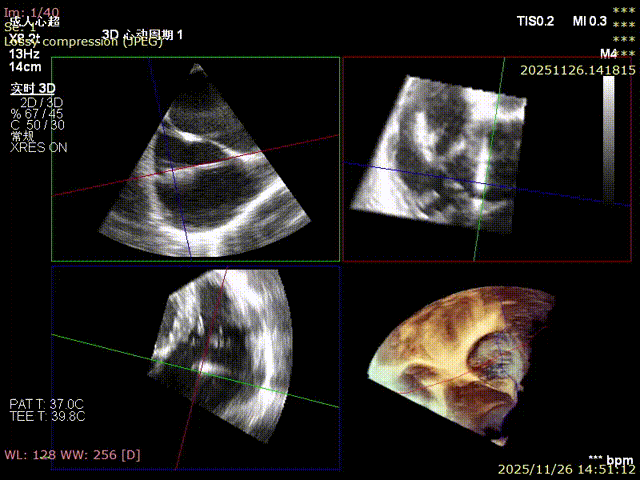

For patients with severe functional tricuspid regurgitation, the cardiovascular team developed a personalized strategy through multidisciplinary consultation and innovatively applied the K-Clip® Transcatheter Tricuspid Annuloplasty System. Intraoperatively, transesophageal echocardiography (TEE) combined with digital subtraction angiography (DSA) was used for imaging guidance. A precise access was established via the right internal jugular vein, and the K-Clip® device was delivered to the tricuspid annulus in the right atrium. After multi‑dimensional imaging localization and confirmation, accurate annuloplasty of the posteroseptal commissure (P‑S commissure) was successfully completed.

Immediate postoperative echocardiographic evaluation showed that tricuspid regurgitation was reduced from severe (4+) to mild (1+), with a 30% reduction in annulus area. No adverse events such as atrioventricular block, valve laceration, or cardiac tamponade occurred intraoperatively or postoperatively. Concurrent right coronary angiography confirmed no compression or distortion of the coronary artery course and normal blood flow perfusion. The patient recovered smoothly after the procedure, and right heart failure symptoms were significantly improved at discharge.